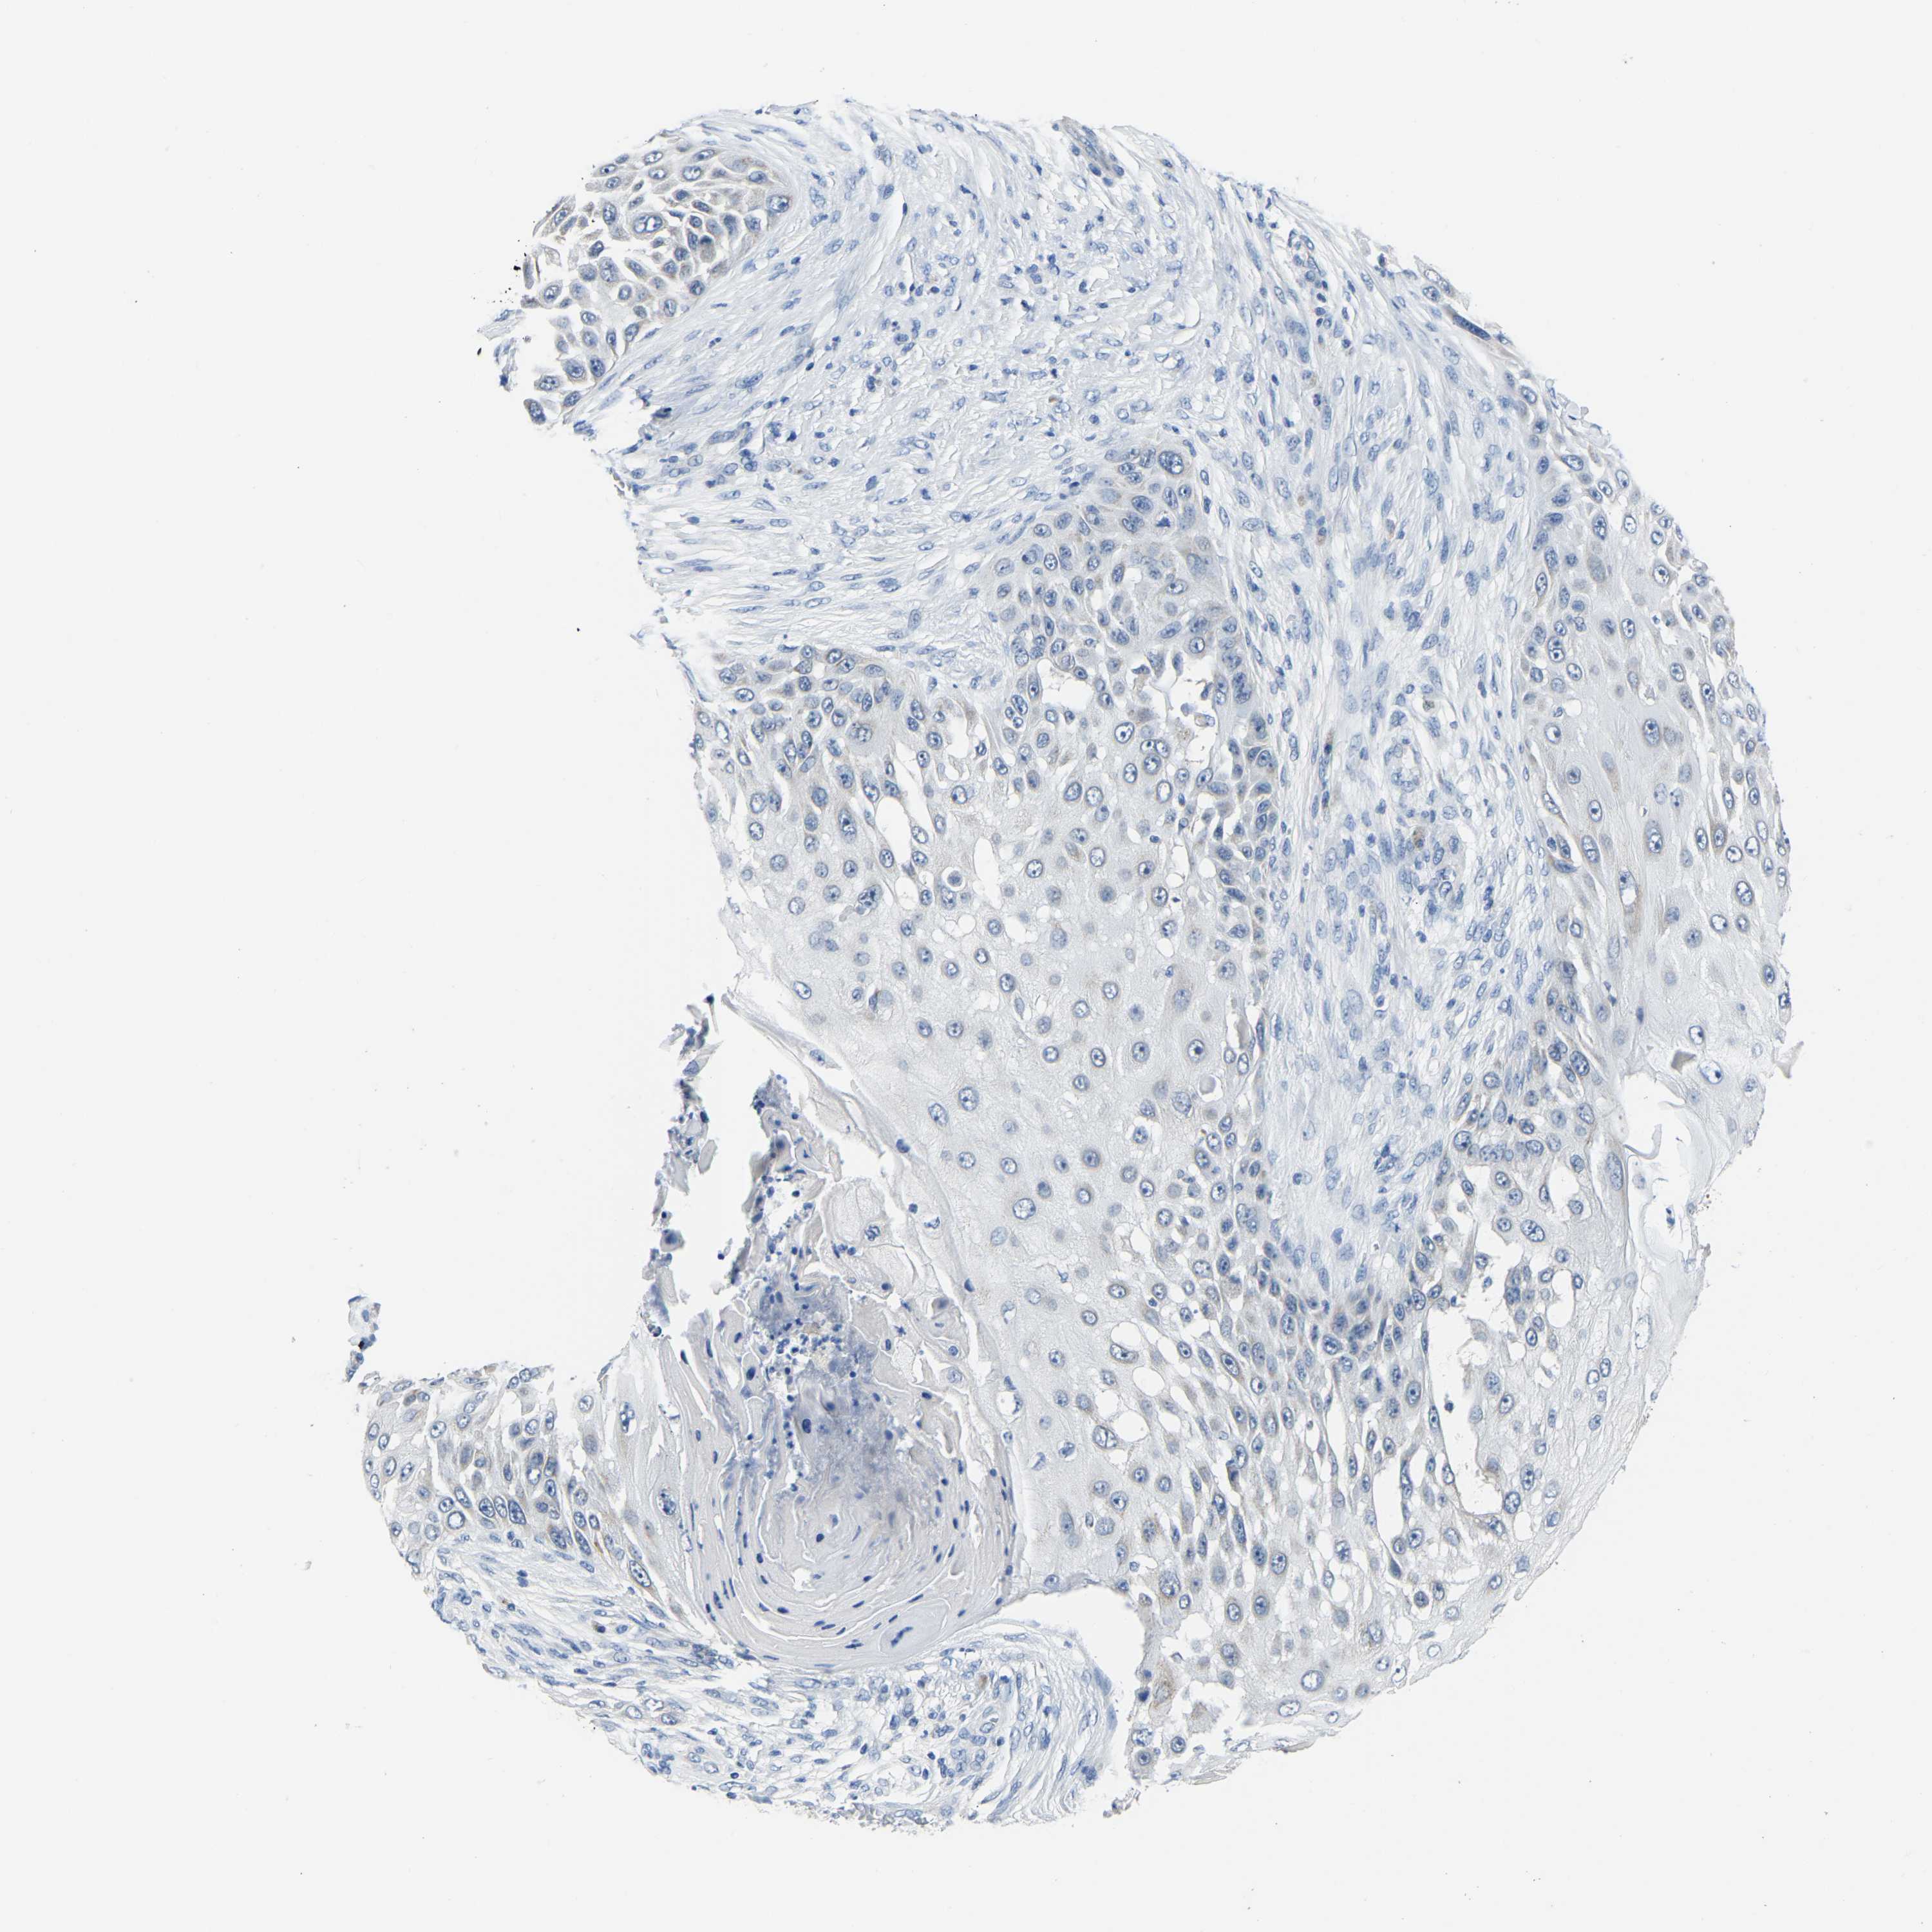

SKIN CANCER - Protein expressioni

A mouse-over function shows sample information and annotation data. Click on an image to view it in a full screen mode. Samples can be filtered based on level of antibody staining by selecting one or several of the following categories: high, medium, low and not detected. The assay and annotation is described here.

Each image is clickable and will lead to virtual microscopy that enables deeper exploration of all samples and also displays staining intensity scores, fraction scores and subcellular localization as well as patient and tissue information for each sample.

Antibody HPA018993

Staining

Not detected

Negative

None

Squamous cell carcinoma, NOS